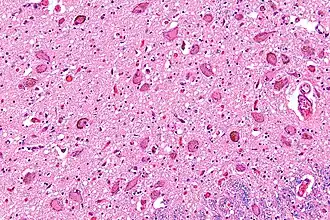

Micrografía mostrando el locus cerúleo. (Tinción luxol fast blue). | ||